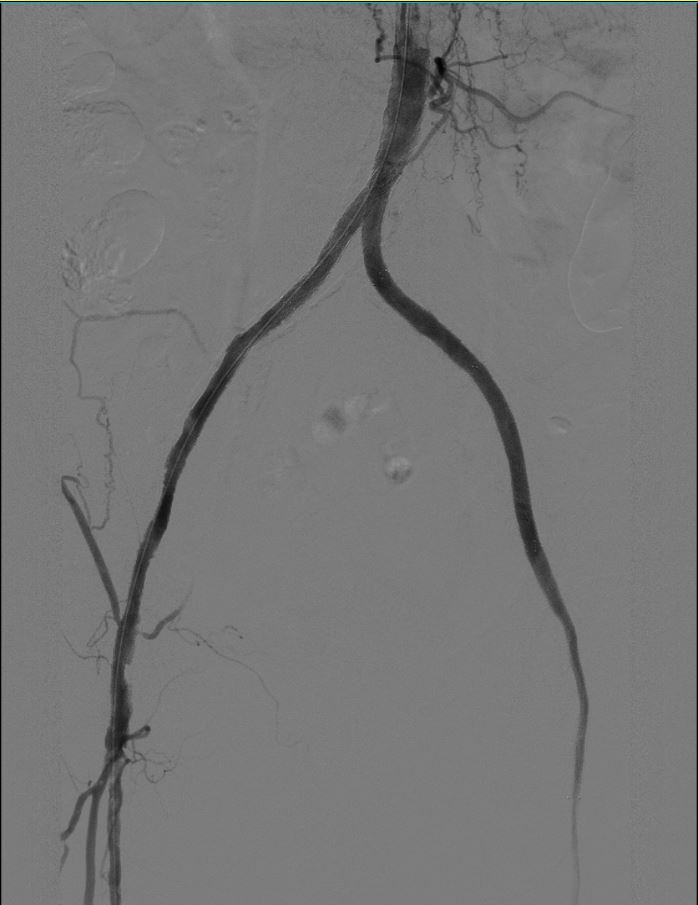

检查结果出来,大家都吓了一跳。从肚子到双腿的大血管,长长一段全堵上了!诊断很清楚:勒里施综合征。 「截肢?」 张爹一听,脑子「嗡」的一声,似乎看见自己坐着轮椅的样子,心凉了半截。

几个科的专家一起商量。经过反复评估和推演,定了方案:上,用创伤小、恢复快的微创手术-腹主动脉-双髂动脉分叉血管腔内覆膜支架重建术(CERAB 技术)!

手术当天,介入手术室里气氛紧张。麻醉由于大朋主任坐镇,车星主任操控着导丝导管,细心打通堵塞的血管。最终,凭借娴熟的技术,把支架精稳稳放进去,血流「哗」的一下通了!

术后立竿见影!张爹摸着瞬间回暖的双腿,激动得不行:「热了!热了!不麻了!」